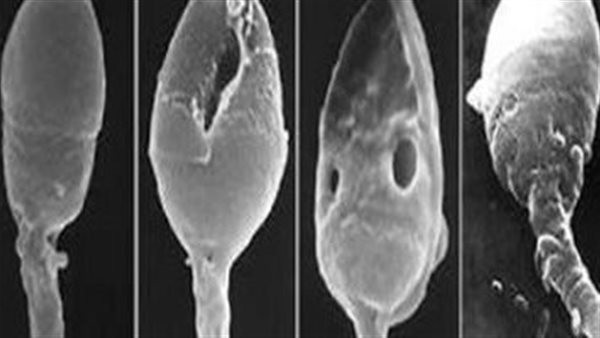

ما هو علاج تشوهات الحيوان المنوي؟.. سؤال هانم يشغل بال العديد من الرجال وزوجاتهم، وخاصة الذين يرغبون في الإنجاب ويواجهون مشكلة في تحقيق ذلك؛ بسبب المعاناة من وجود تشوهات بالحيوانات المنوية؛ لذا سنتعرف خلال السطور التالية على ما هو علاج تشوهات الحيوان المنوي؟.

وللإجابة عن سؤال ما هو علاج تشوهات الحيوان المنوي؟، يؤكد الدكتور خالد زين، استشاري جراحات المسالك البولية وأمراض الذكورة والعقم والضعف الجنسي، أنه من الممكن علاج تشوهات الحيوانات المنوية المؤقتة، وخاصة الناجمة عن اتباع عادات يومية

وغذائية خاطئة، مثل تلك التي تنتج عن الإصابة بالحمى أوالعدوى، إذ يبدأ الرجل في إنتاج الحيوانات المنوية الطبيعية مرة ثانية فور العافي من هذه الحالات، منبهًا إلى أنه في حال كانت تشوهات الحيوانات المنوية ناجمة عن العوامل الوراثية فقد يصعب علاجها.

ويضيف استشاري جراحات المسالك البولية وأمراض الذكورة والعقم والضعف الجنسي، أنه لا يمكن أيضًا علاج تشوهات الحيوانات المنوية التي تنجم عن العلاج الكيميائي والإشعاعي؛ لذا قد يقترح الطبيب تجميد الحيوانات المنوية قبل أن يبدأ في هذه العلاجات لاسيما في حال كان المريض ينوي الإنجاب مستقبلًا.